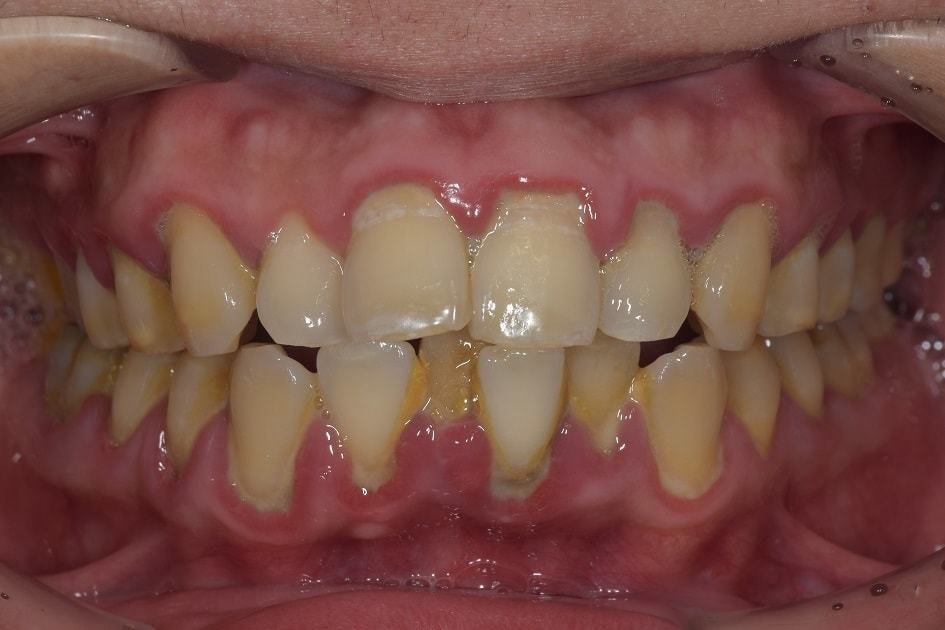

上の写真は、当院に初めて来られた時の状態です。初診時は歯石も多く、歯ぐき、特に歯の付け根が赤く炎症しているのがわかるかと思います。

こちらの写真は、当院での基本的な歯周病治療を行った後の状態になります。

赤かった歯茎がある程度健康なピンク色に変化していることがよくわかるかと思います。ここから本格的な歯周病治療が必要ですが、本格的な治療を始める前にある程度炎症のとれた歯茎にしておくことは、非常に大切です。